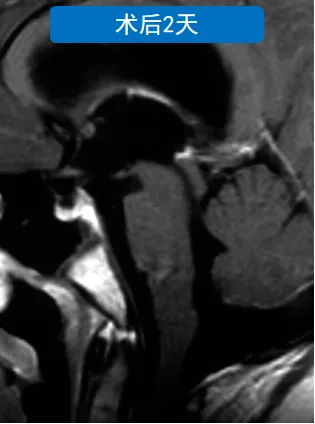

术后患儿临床症状显著改善,头痛呕吐症状消失。病理检查确诊为WHO III级室管膜瘤,术后辅以放化疗综合治疗。五年随访期显示肿瘤无复发征象,患儿神经功能保留完整。